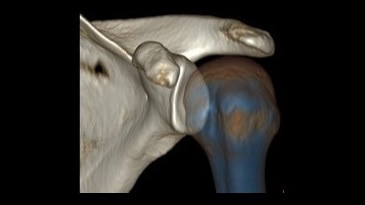

Kas-İskelet Görüntü Galerisi